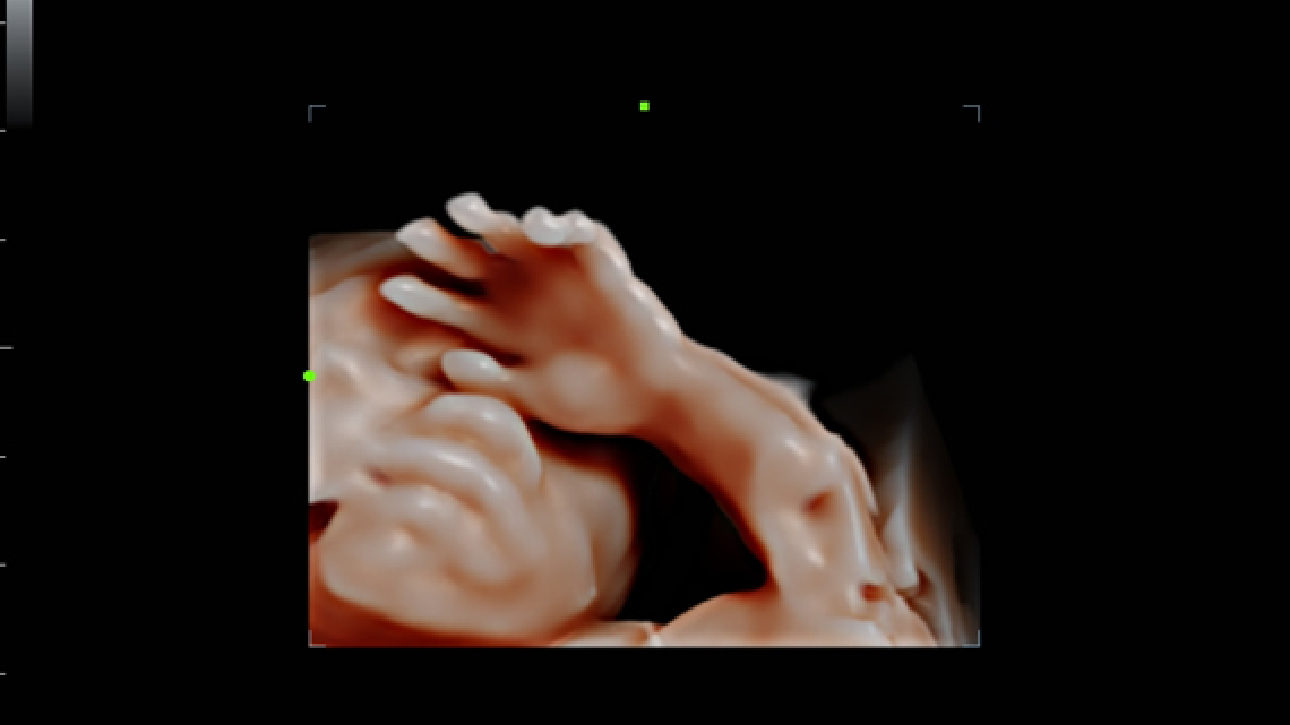

ImĂĄgenes clĂnicas